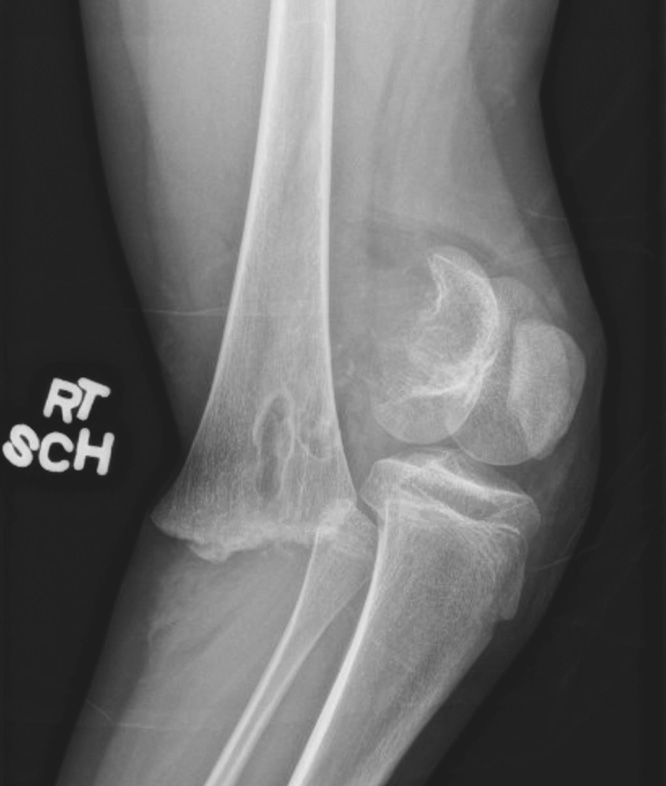

Рентген показал перелом дистального отдела правой бедренной кости с сильным смещением и повреждением зоны роста (рис. 2). При осмотре была выявлена колотая рана в задней части бедра, выстояние надколенника, рекурвация конечности и ее вынужденное сгибание в коленном суставе. Рот пациентки был относительно маленьким, но не было отмечено аномалий нёба или сколиоза. Периферическая чувствительность и разгибательная функция большого пальца стопы нарушены не были. Пульс на тыльной артерии стопы с двух сторон ощущался пальпаторно на 3+ и был подтвержден допплерографически. Лодыжечно-плечевой индекс правой и левой нижних конечностей составил 1,2 и 1,1 соответственно. Родители пациентки были уведомлены о возможном нарушении роста. Вакцинация против столбняка была проведена своевременно. Перед операцией был введен 1 г цефазолина внутривенно.

Рис. 2. Рентгенограмма правого коленного сустава в боковой проекции, показывающая перелом дистального отдела бедренной кости Салтер – Харриса 2-го типа со смещением